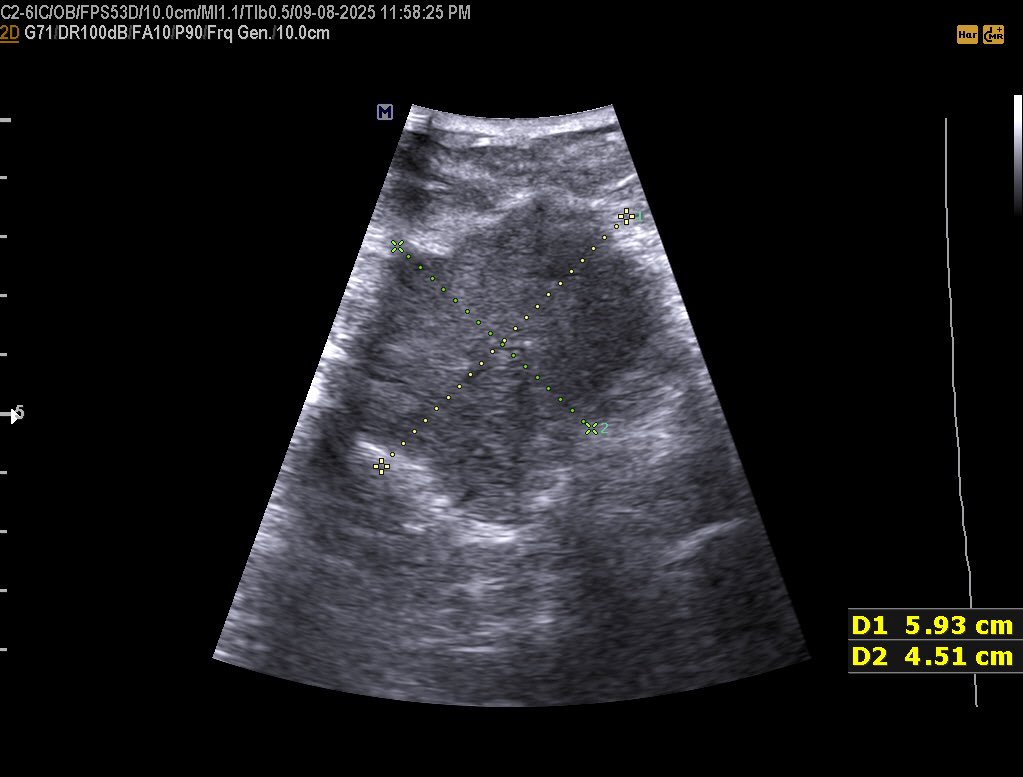

28 years female presented with non-specifc abdominal pain. This mass seen just posterior to the Stomach and left lateral to the abdominal aorta , your opinion? #EchoTech

28 years female presented with non-specifc abdominal pain. This mass seen just posterior to the Stomach and left lateral to the abdominal aorta , your opinion? #EchoTech